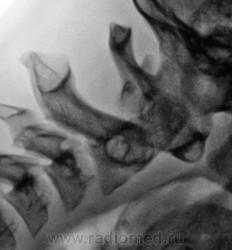

Согласен с мнением Валентина Львовича - сегмент вызывает сомнения. Щель атланто - осевого сустава должна быть шириной около 2 мм и иметь одинаковую ширину на всем протяжении. В данном случае - явное расширение щели в верхних отделах. Так что по крайней мере - нестабильность - прощай Дзю-до...

Кроме этого - структура зуба - это артефакты или...

У Садофьевой:

"Критерием нормы анатомических соотношений в срединном атлантоосевом суставе является высота рентгеновской суставной щели не более 2 мм, одинаковая на всем протяжении. Однако следует учитывать, что данный критерий действителен только при выполнении рентгенограммы в правильной укладке, т. е. при среднем положении головы. На рентгенограммах, произведенных при сгибании или разгибании шеи, рентгеновская суставная щель срединного атланто-осевого сустава может приобретать клиновидную форму и в норме."

Но меня учили, что у детей ширина щели срединного атланто-осевого сустава в норме до 4 мм (у взрослых - 2), что подтверждено личной практикой.

2. Определение переднего атлантоаксиального промежутка. Это расстояние между внутренней поверхностью передней дужки позвонка СI и передней поверхностью зубовидного отростка позвонка СII (сустав Крювелье). В норме у взрослого при сгибании головы вперед этот промежуток не превышает 3 мм, а у ребенка 5 мм. При увеличении этого расстояния можно подозревать передний подвывих.

Часто встречаю Ваши заключения, очень нравятся....

Я больше насторожен на плавность перехода в позвоночный канал со стороны Блюменбахова ската. Базион должен в норме быть точно над вершиной зуба С2, а линия входа - плавной. В данном наблюдении - явное смещение Базиона кпереди на весь поперечник зуба! И ступеннеообразная деформация линии входа. Тот показатель о котором пишете Вы - продольный размер позвоночного канала - из этой же "оперы". Но измерять его нужно именно тогда, когда это патологическое состояние проявляется - то есть при нагрузке (в данном случае - сгибании!!!) А стоя с прямой шеей - все будет в норме!

Так что считаю, что, независимо от того, что мы увидим на снимке в стандартной боковой проекции, в нашем случае нестабильность есть, и игнорировать ее в плане спорта - никак нельзя, но клиническое ее значение должно быть оценено опытным вертебрологом...